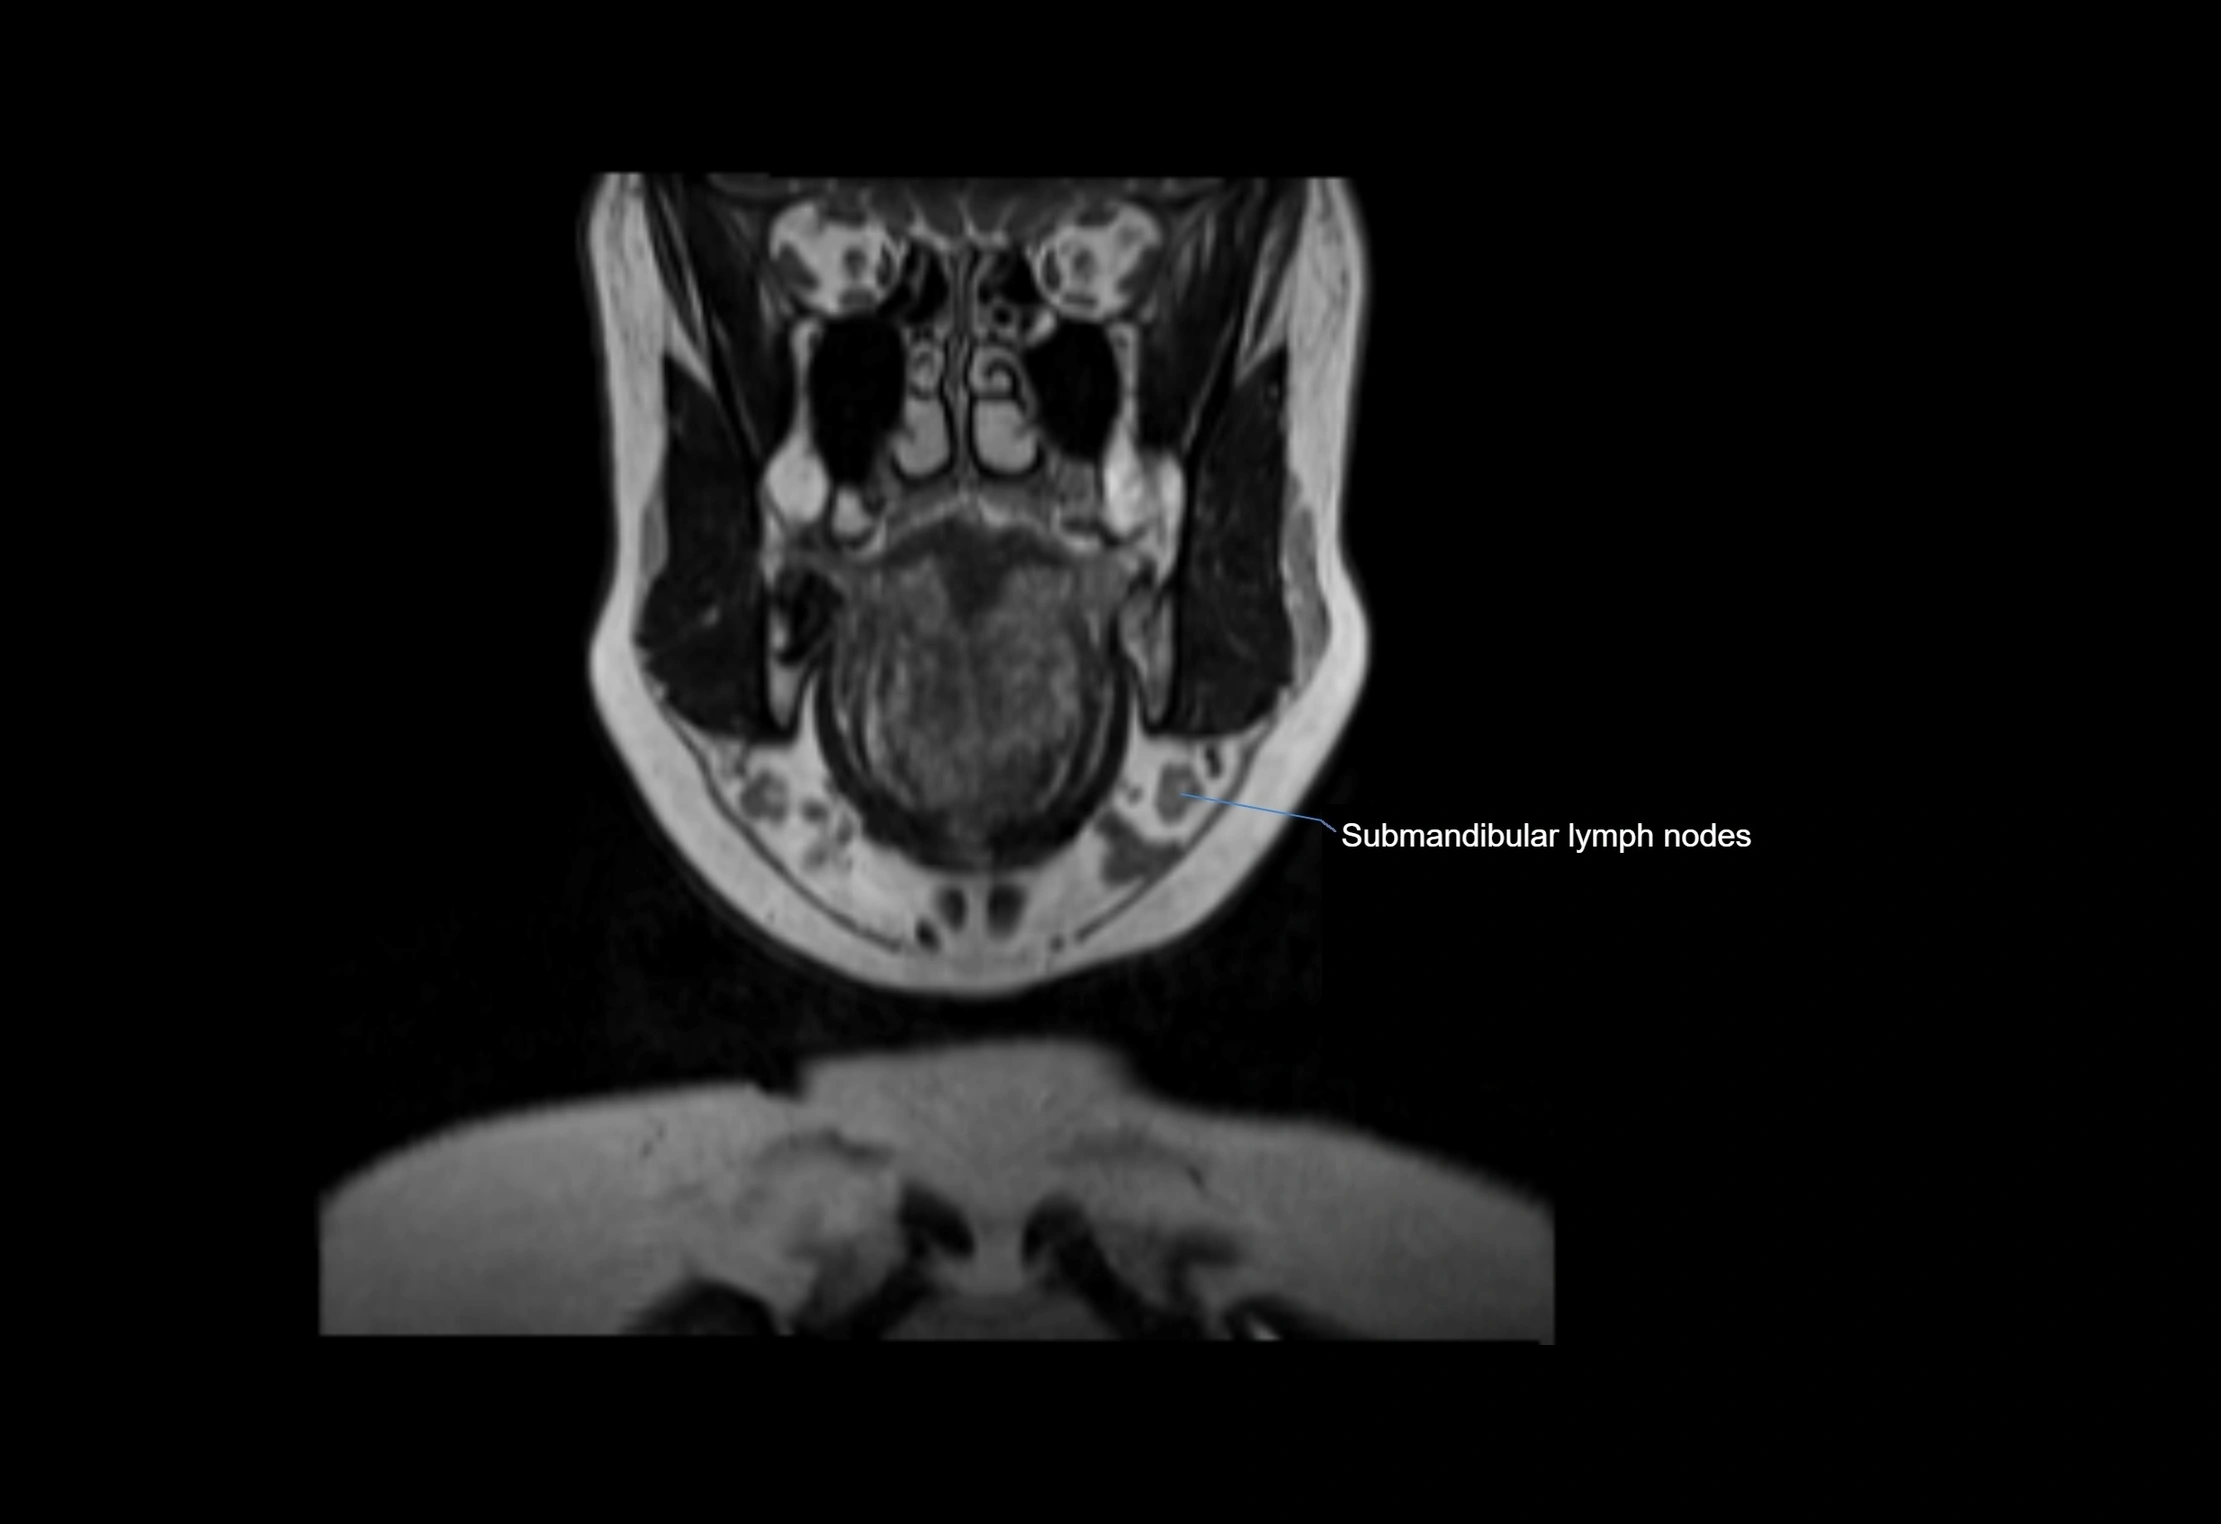

Location

• Found along primary lymph node chains, including preauricular, submandibular, parotid, and occipital regions

• Embedded in subcutaneous fat or superficial fascia, often lateral or posterior to primary nodes

MRI Appearance

T1-weighted images:

• Normal accessory nodes appear as small, oval hypointense to intermediate signal structures within subcutaneous fat

• Surrounded by hyperintense fat, enhancing contrast for visualization

• Pathological nodes may appear enlarged or rounded, sometimes with cortical thickening

MRI images